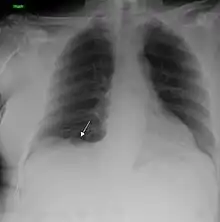

| A chest X-ray showing a tumor in the lung (marked by arrow) | |

Performing a chest radiograph is one of the first investigative steps if a person reports symptoms that may be suggestive of lung cancer. This may reveal an obvious mass, the widening of the mediastinum (suggestive of spread to lymph nodes there), atelectasis (lung collapse), consolidation (pneumonia), or pleural effusion.[15] CT imaging of the chest may reveal a spiculated mass which is highly suggestive of lung cancer, and is also used to provide more information about the type and extent of disease. Bronchoscopic or CT-guided biopsy is often used to sample the tumor for histopathology.[13]

Lung cancer often appears as a solitary pulmonary nodule on a chest radiograph. However, the differential diagnosis is wide. Many other diseases can also give this appearance, including metastatic cancer, hamartomas, and infectious granulomas caused by tuberculosis, histoplasmosis or coccidioidomycosis.[65] Lung cancer can also be an incidental finding, as a solitary pulmonary nodule on a chest radiograph or CT scan done for an unrelated reason.[66] The definitive diagnosis of lung cancer is based on the histological examination of the suspicious tissue[2] in the context of the clinical and radiological features.[12]